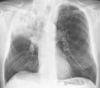

* Pulmonary Edema secondary to CHF * A great deal of accentuated interstitial markings, curly lines, and an enlarged heart. * Normally indistinct upper lobe vessels are prominent but are also masked by interstitial edema.

117